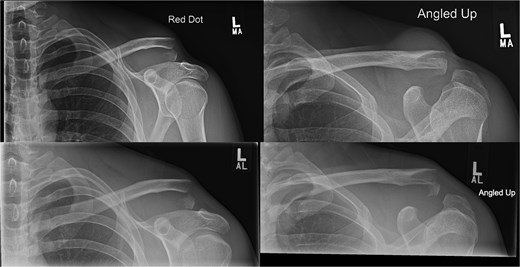

A 15-year-old male sustained a displaced Neer type IV lateral clavicle fracture during a rugby match, presenting with acute pain, deformity, and dorsal displacement without neurovascular compromise (Fig. 1). Imaging confirmed the diagnosis, and open reduction with TightRope and Fiber-wire reinforcement was performed. Early rehabilitation was initiated following short-term immobilization. At 6 weeks, the patient achieved pain-free shoulder function and radiographic stability. By four months, he regained full range of motion and returned to non-contact sports. Minor peri-scar numbness persisted, but imaging confirmed fracture union, and he was cleared for contact activities (Fig. 2A–B).

Radiographs of first case showing a displaced Neer type IV lateral clavicle fracture with deformity and displacement.